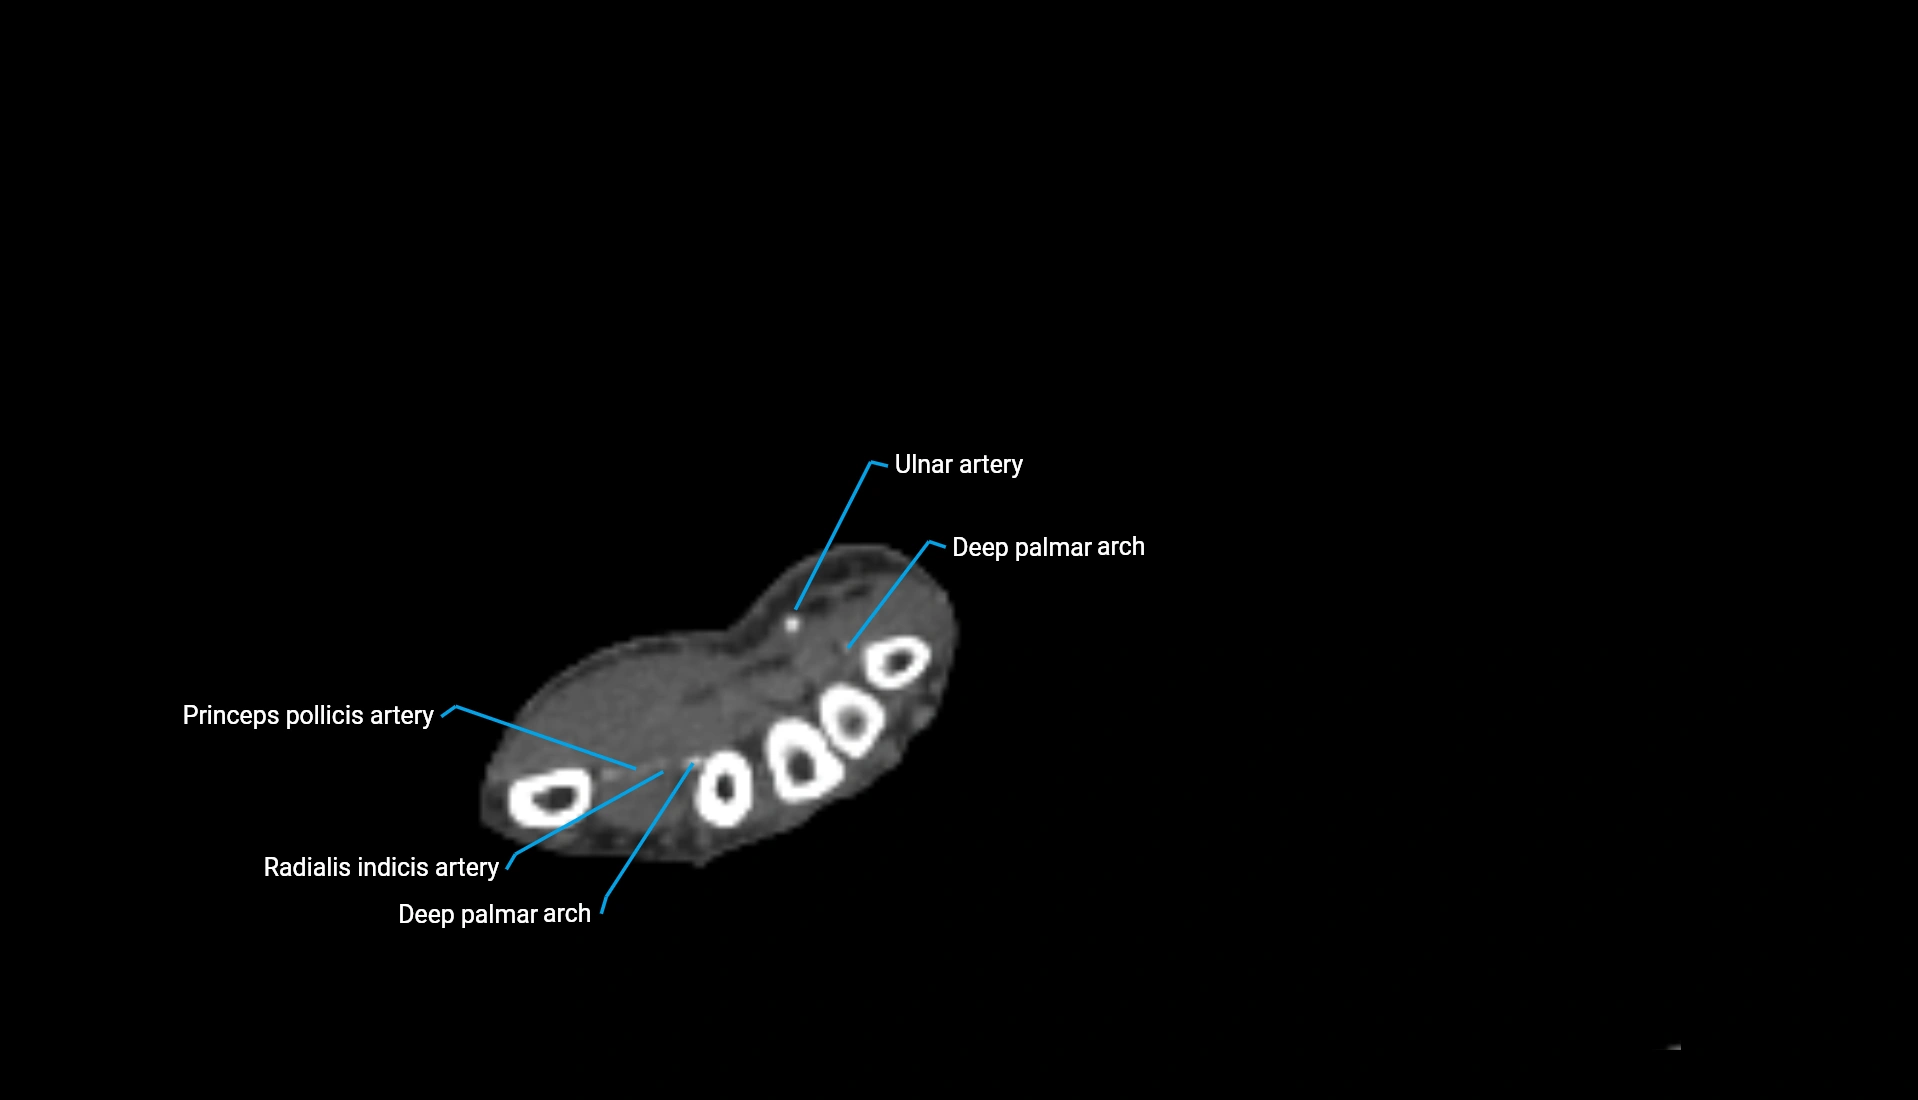

CT Appearance

Non-Contrast CT:

• Cortex: High-density, sharply defined

• Subchondral bone: Dense cancellous matrix

• Articular surface: Smooth concave contour articulating with the capitellum

• Excellent for evaluating bone integrity, alignment, and subtle fractures

Post-Contrast CT:

• Bone: No enhancement

• Joint capsule and synovium: Mild enhancement outlining the joint

• Improves contrast between soft tissues and bony margins

• Useful in detecting subtle joint abnormalities or postoperative changes